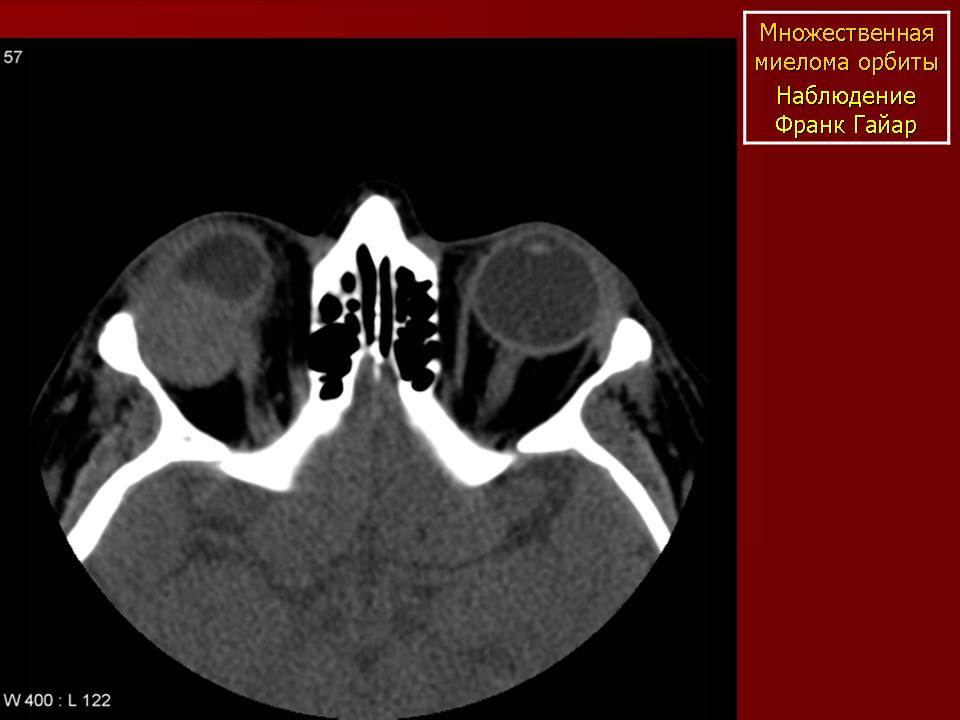

Миелома Пнд, 19/09/2011 - 00:49 #1 Катенёв Валенти... Не на сайте Был на сайте: 7 лет 3 месяцев назад Зарегистрирован: 22.03.2008 - 22:15 Публикации: 54876 Плазмоцитома орбиты Приложения:

Плазмоцитома орбиты